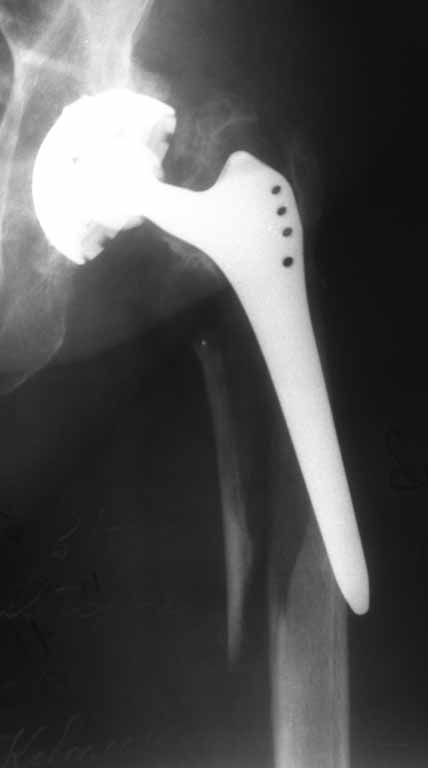

Перипротезный перелом бедра |

Пациентка 86 лет. Травма в результате падения.

планируется замена ножки на ревизионную + серкляжи на отломки. Может что нибудь еще?